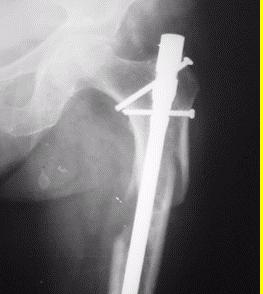

Manejo ortopédico de la artropatía hemofílica en México. Por: Dr. Armando R. Hernández Salgado, Ortopedista y Traumatólogo, Cirujano de Artroscopia y Cirugía de Rodilla, Especialista en Artropatía Hemofílica, Asesor Voluntario de FHRM. Pág. 109